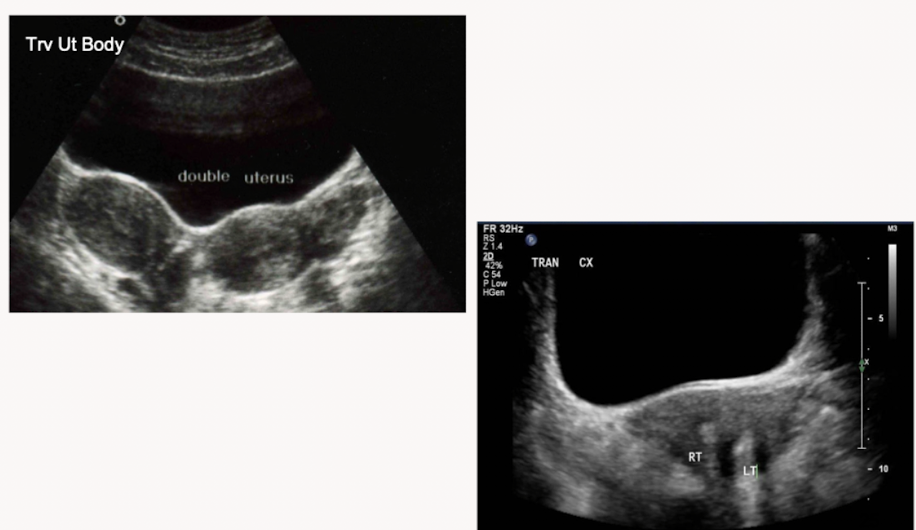

Name the uterine anomaly

Uterus didellphys: failure of fusion resulting in 2 uteri, 2 cervices and 2 vaginal canals

Best proved in transverse

Unicornute uterus: usually only has one functioning fallopian tube. May have a rudimentary horn